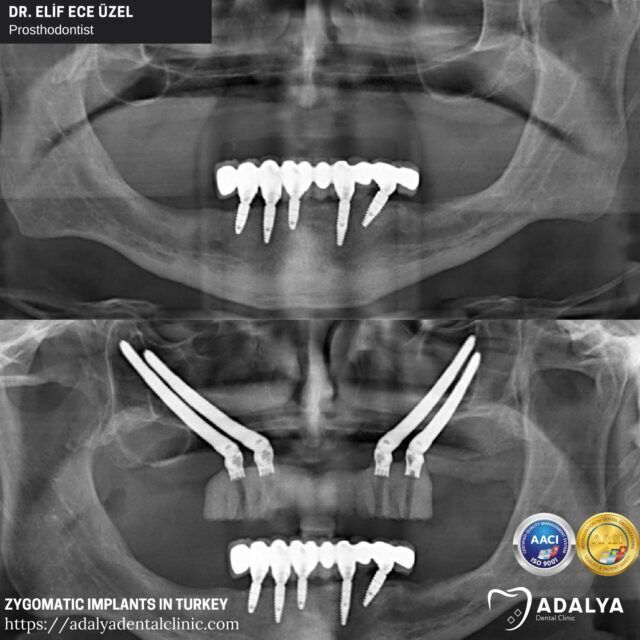

Zygomatic implants are longer than traditional dental implants, allowing them to anchor into the cheekbone (zygoma) instead of the jawbone. This alternative technique eliminates the need for bone grafting and lengthy healing periods, providing a quicker and more streamlined process.

Zygomatic implants are a revolutionary dental solution designed to address severe cases of tooth loss or bone loss in the upper jaw. Unlike traditional dental implants that rely on the jawbone for support, zygomatic implants are anchored into the cheekbone (zygoma), a stronger and more stable structure.

The length of zygomatic implants, which can range from 30 to 55 millimeters, allows them to extend beyond the upper jaw and into the cheekbone, providing a secure and reliable foundation for dental prosthetics. This game-changing technology has opened up new possibilities for individuals who were previously deemed unsuitable for traditional implants due to inadequate bone volume or quality.

To determine if you are a candidate for zygomatic implants, your dentist or oral surgeon in Turkey, Antalya will conduct a thorough evaluation, which may include a comprehensive dental examination, X-rays, and advanced imaging techniques like CT scans. These diagnostic tools will help assess the condition of your jawbone and cheekbone, as well as identify any potential anatomical considerations that may impact the placement of the zygomatic implants.

- Implant placement: Using specialized surgical guides and techniques, the surgeon will carefully drill and prepare the cheekbone to receive the zygomatic implant. The implant is then securely placed into the zygoma.